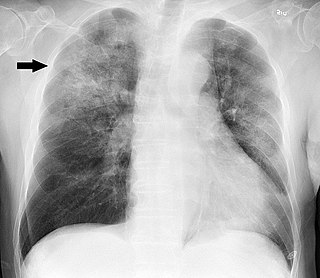

Hidrocortisona para reducir la mortalidad en la neumonía grave

En este ensayo clínico doble ciego, los pacientes con formas graves de neumonía adquirida en la comunidad ingresados en UCI y tratados con 200 mg diarios de hidrocortisona tuvieron un riesgo menor de mortalidad a los 28 días que los que recibieron placebo. New England Journal of Medicine, 21 de marzo de 2023.